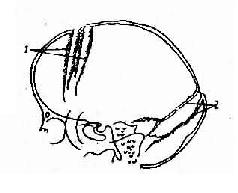

图2-23 儿童颅内高压所致颅缝分离

1.冠状缝 2. 人字缝

2.颅缝分离是儿童患者颅内压增加的重要表现。由于儿童的颅缝尚未骨化,所以当颅内压增加时即可分离。